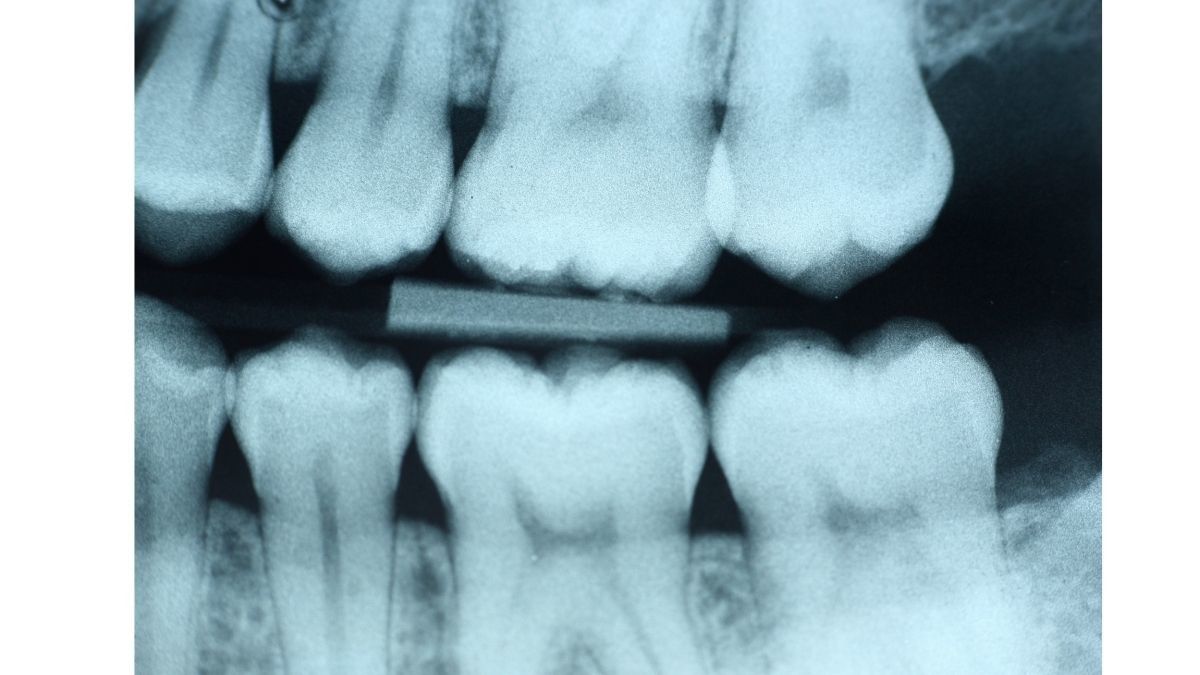

3. Kerusakan Dentin

Dentin merupakan lapisan gigi yang berada di bawah email. Gigi berlubang yang tidak segera ditambal, bisa menyebabkan kerusakan pada dentin.

Kerusakan dentin akan membuat sensitivitas gigi ekstrem saat Anda minum minuman manis yang panas atau dingin, serta saat makan.

Kerusakan dentin yang cepat teridentifikasi bisa diperbaiki dengan menambal gigi. Namun, jika kerusakan telah parah, maka dokter gigi akan menghilangkan bagian gigi yang membusuk dan membuat mahkota baru di atas struktur gigi yang tersisa.